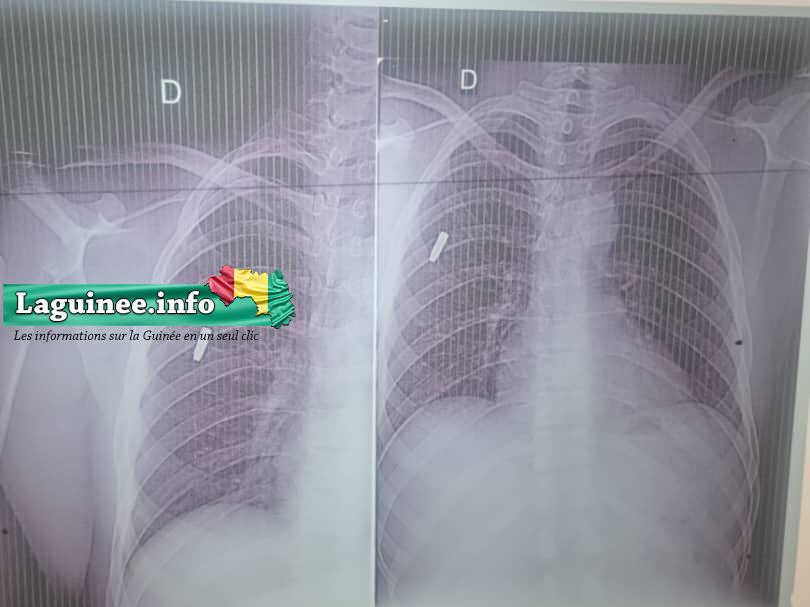

« Ce lundi 11 juillet 2022, nous avons reçu deux bonhommes grièvement blessés par balles aux environs de 14h entre les districts de Soumbarakôba et Manitro, les deux localités relèvent de la sous préfecture de Doko. Selon les témoins qui ont assisté à la scène et qui ont transporté aux services des urgences de l’hôpital préfectoral de Siguiri, les deux hommes ont été tirés à bout portant laissant leur moto. Ils ont réussi à prendre leurs sacs. Parmi les blessés, la première personne répond au nom de Morynfing Diakité âgé de 30 ans environ cultivateur résidant à Kôdjou. Il à eu comme diagnostic, une plaie pénétrante de l’omoplate droite par arme à feu. La deuxième personne s’appelle Kaba Sidibé âgé de 38 ans cultivateur également à Kôdjou. Comme diagnostic, une plaie transfixiante par arme à feu sur la cuisse droite. Et pour le moment je dirais que ces deux personnes sont hors du danger. Concernant le cas de Morynfing Diakité, il doit être référé dans un centre très spécial pour un tel traitement parce que la balle est très mal placée. Il sera envoyé à Bamako pour le retrait de la balle. Nous avons fait les visites radio et toutes les conditions y ont été mises en place pour leur survie et Dieu merci l’équipe à réussi à le faire », a fait savoir le médecin Aboulaye Bachir Condé du service des urgences de l’hôpital préfectoral de Siguiri .